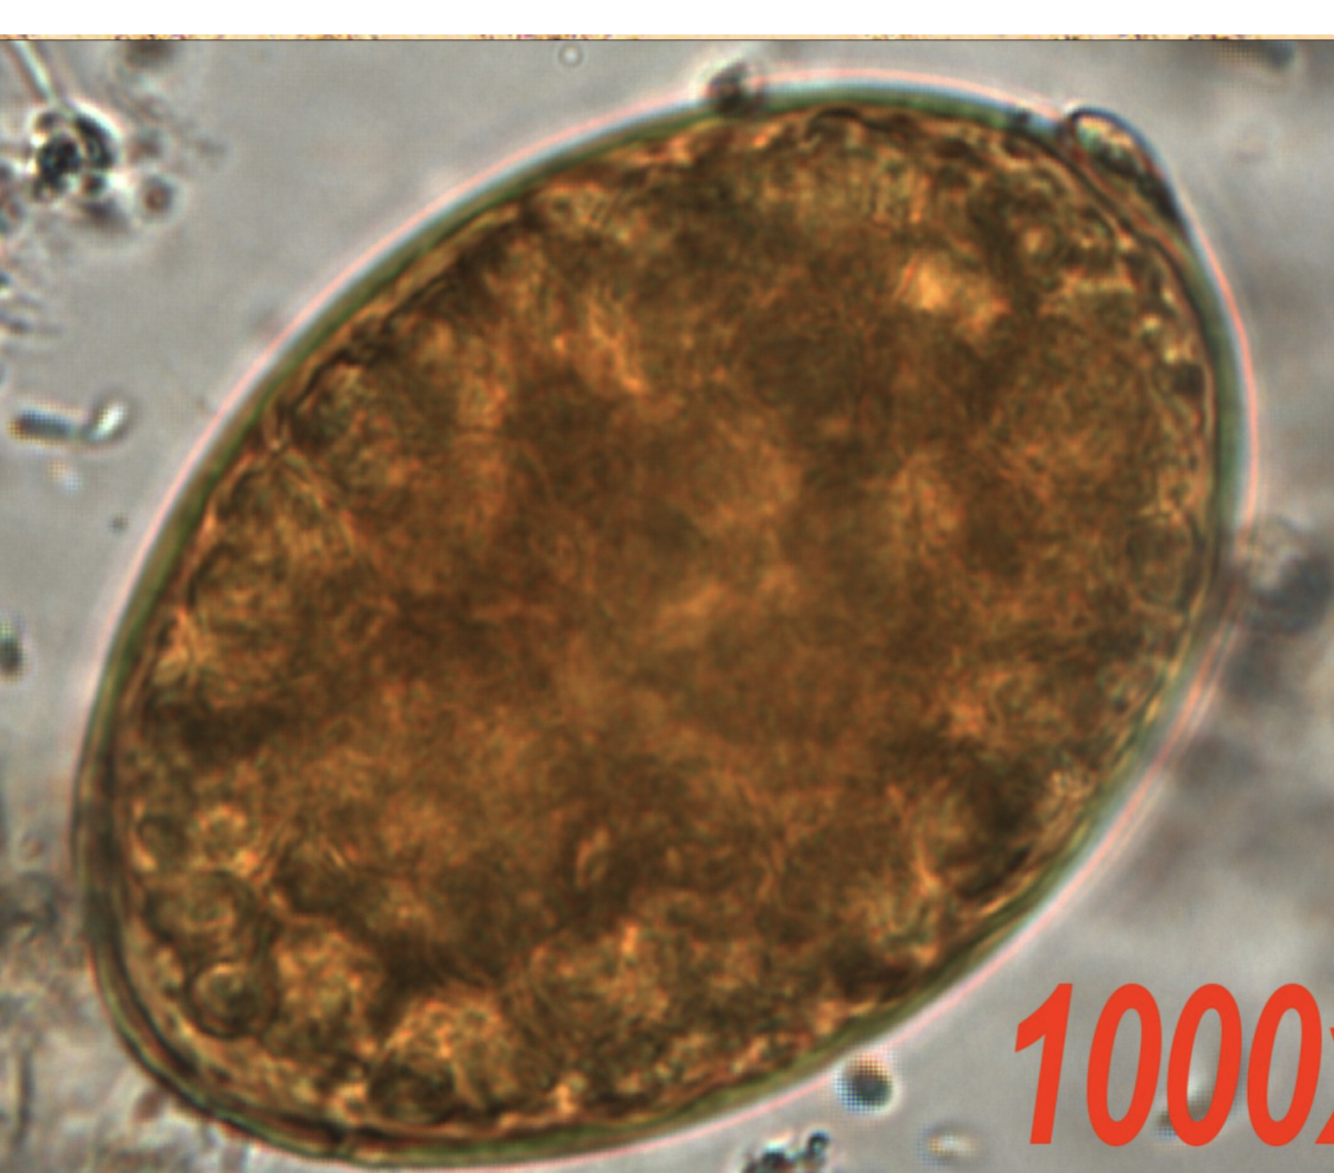

Describe Taenia species’ eggs

A

• Round

• 30-43 microns

• thick cell wall with radial striations

• inside of embryonated egg 6-hooked oncosphere (refer to image)